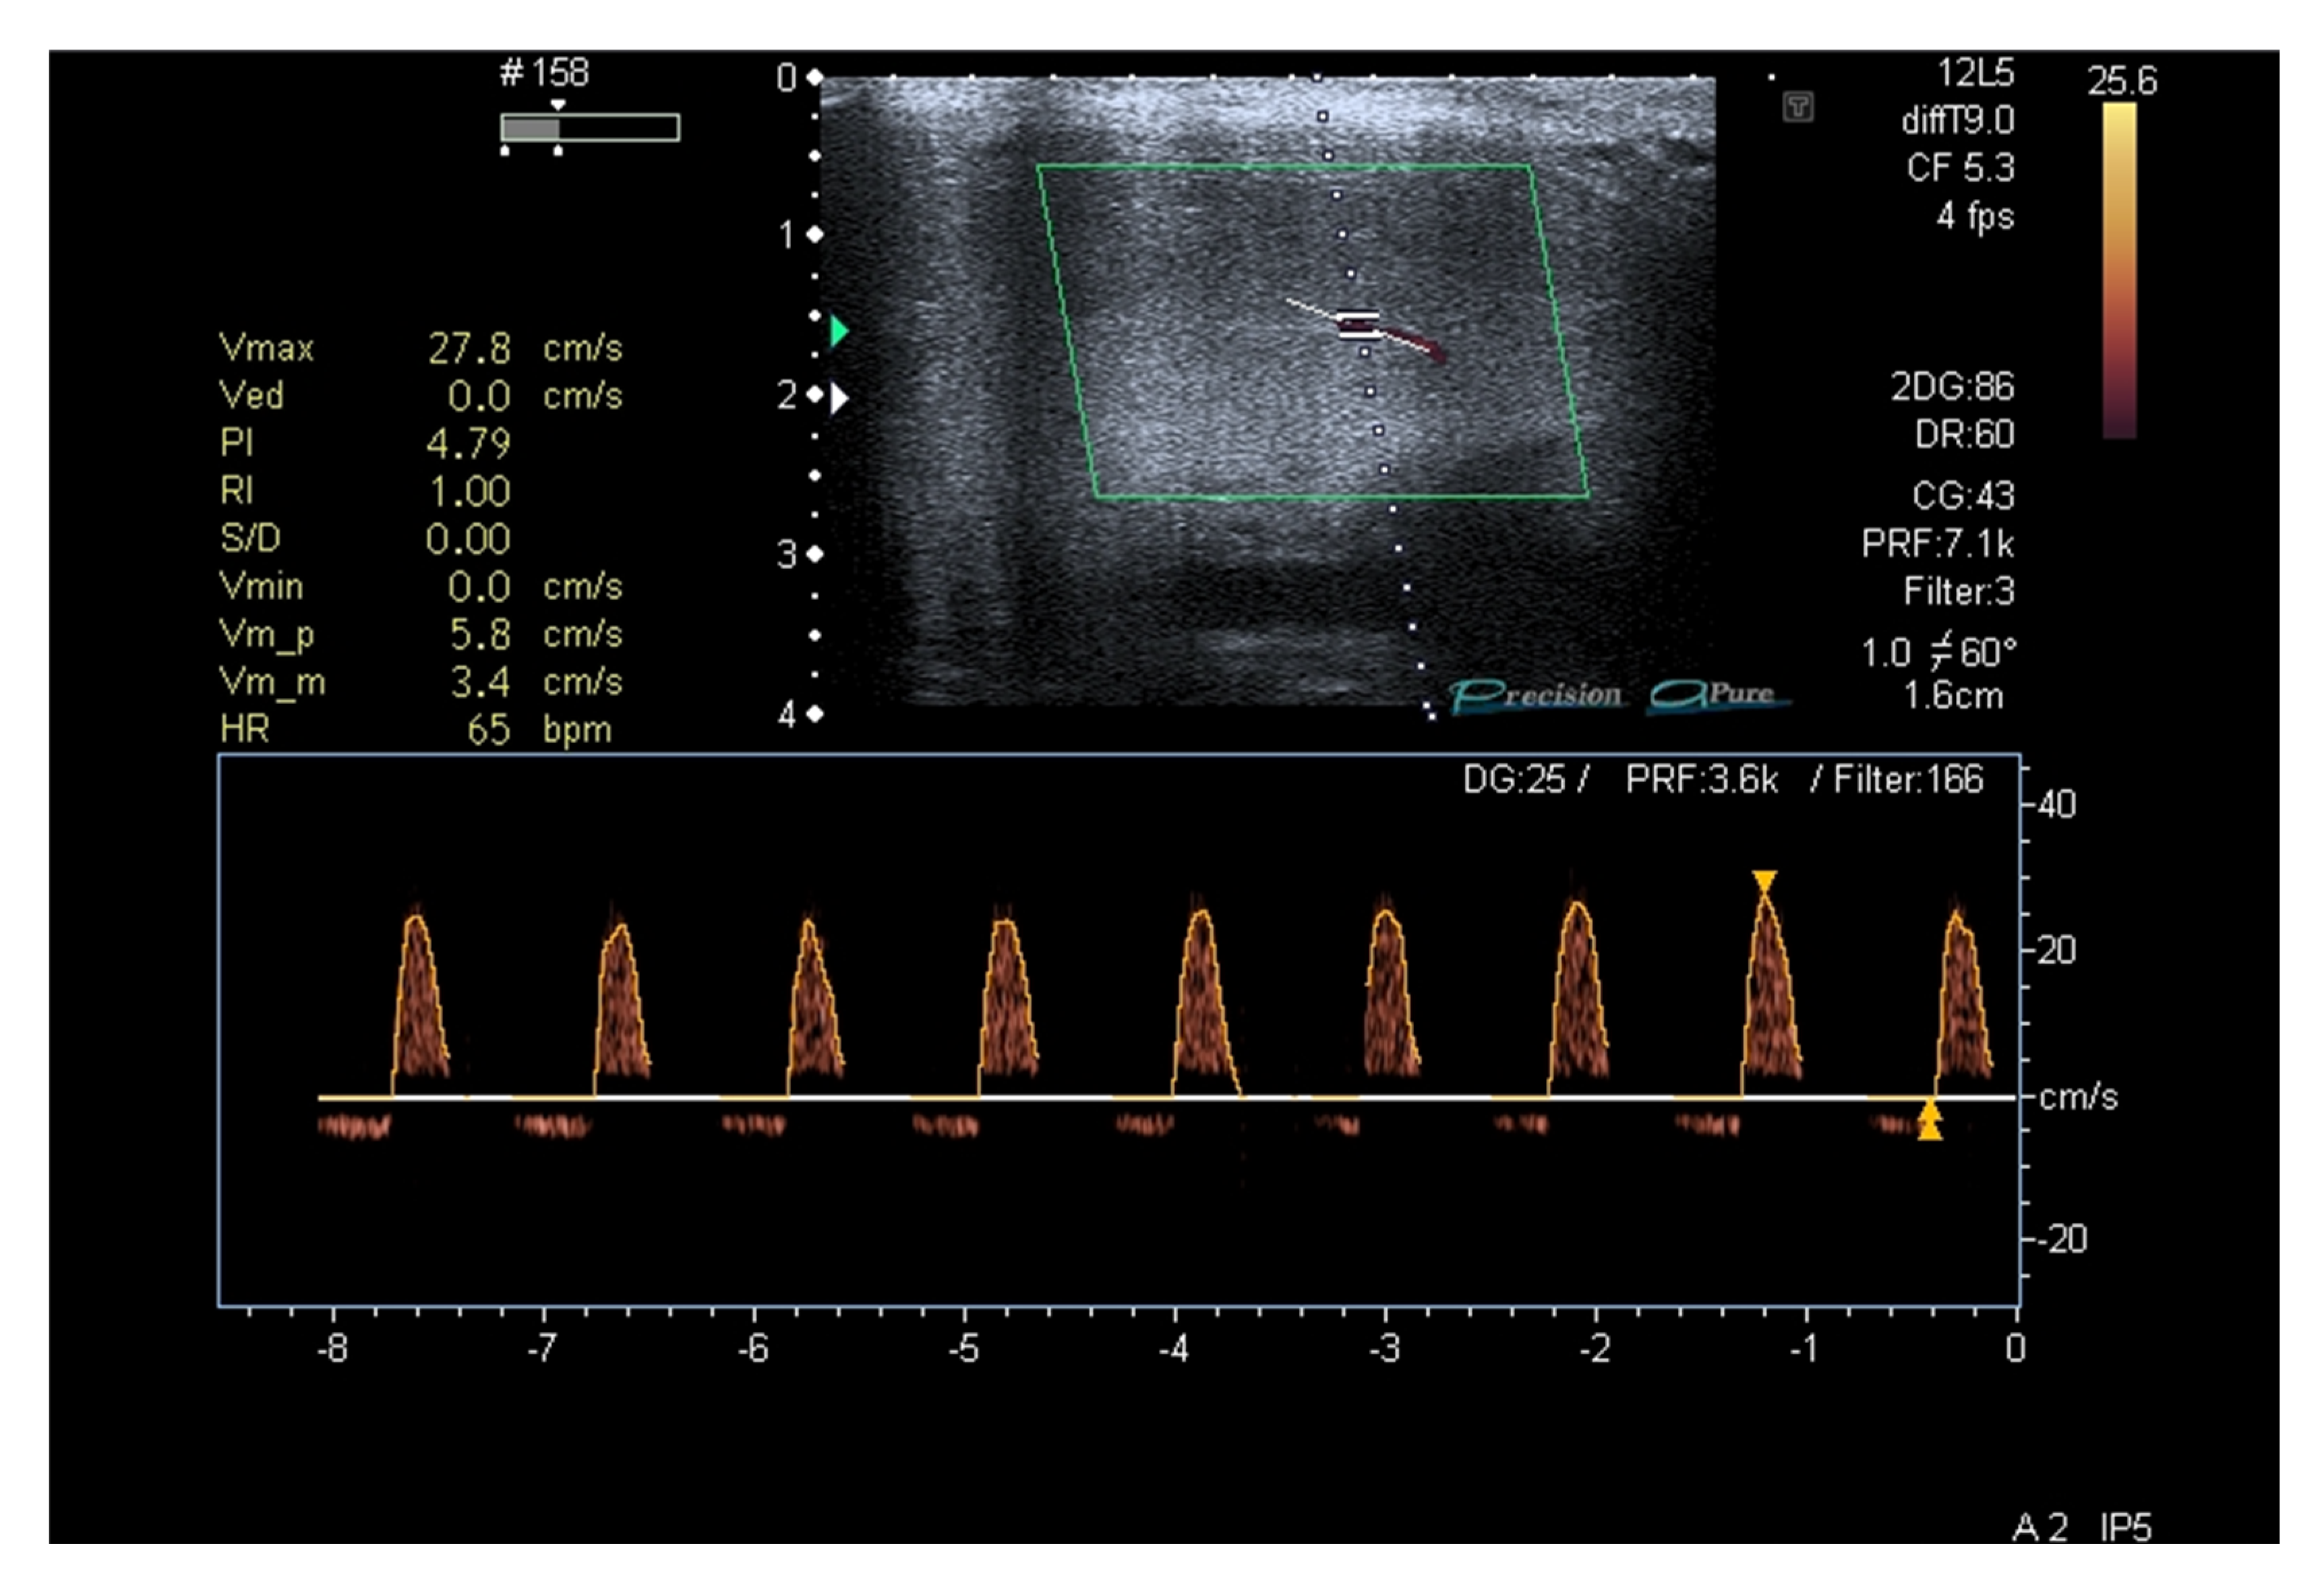

Because of a persisting incomplete response to PDE-5i, after 30 days with sildenafil 100 mg on demand, a penile duplex ultrasound was performed (8 weeks since the patient’s first visit) to assess potential penile vascular impairment [32]. After injection of Alprostadil 20 mcg, a mild reduction in systolic peak flow velocity was found (Figure 2).

Figure 2.

Penile duplex ultrasound at baseline (2 months since patient’s first visit).

In the case here reported by our group, at first, we had no clinical explanation for the etiology of ED other than the possibility of endothelial damage in the penile vascular tissue. This hypothesis was confirmed by the first penile ultrasound performed after two months of poor responsiveness to PDE-5is.